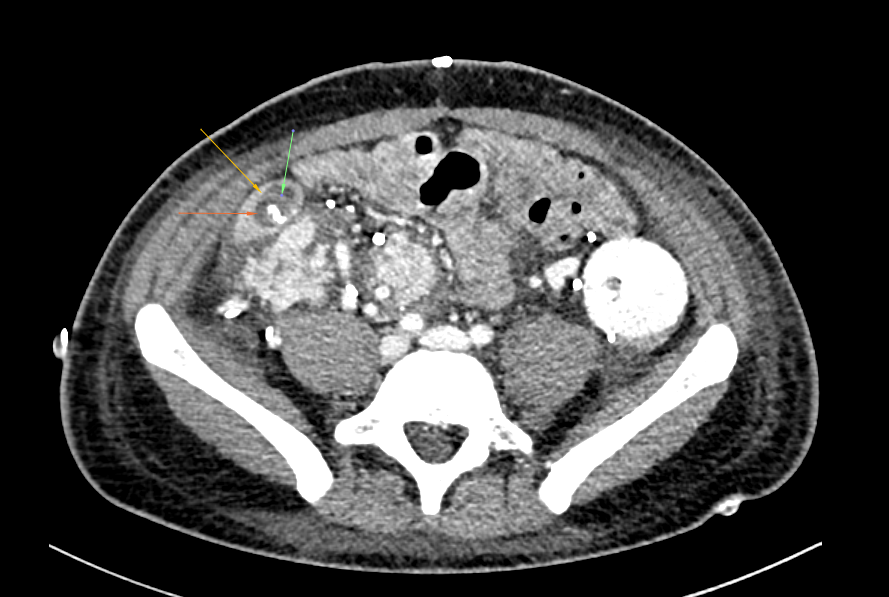

Case N°1 - 33-year-old man with 30-year history of T1DM who developed ESRD and has been dependent on hemodialysis since 2007. The patient underwent a deceased-donor SPK in July 2017. On the 4th postoperative day, he developed hematochezia. Computer tomography angiography revealed active bleeding from enteric anastomosis.

Case N°2 - 31-year-old man with 28-year history of T1DM who developed ESRD and has been dependent on hemodialysis since 2019. The patient underwent a deceased-donor SPK in December 2022. On the 5th postoperative day, he developed hematochezia. Blood count decreased 5% within 24 hrs. Computer tomography angiography revealed active bleeding from enteric anastomosis.